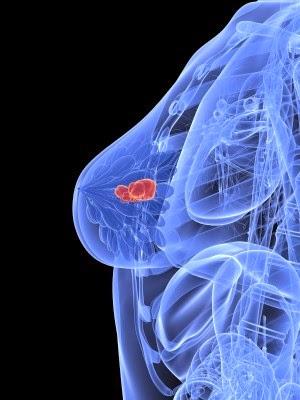

Metales como el aluminio han sido relacionados con el cáncer

de mama desde hace algún tiempo, pero una nueva investigación confirma la

existencia de una clase completamente nueva de estrógenos que causan cáncer conocidos como "metaloestrógenos",

y que se encuentran en miles de productos de consumo - algunos de las cuales

aún se usan en suplementos y alimentos como "nutrientes" ...

Metales como el aluminio han sido relacionados con el cáncer

de mama desde hace algún tiempo, pero una nueva investigación confirma la

existencia de una clase completamente nueva de estrógenos que causan cáncer conocidos como "metaloestrógenos",

y que se encuentran en miles de productos de consumo - algunos de las cuales

aún se usan en suplementos y alimentos como "nutrientes" ...

Un nuevo estudio publicado en la revista Cancer Research revela que la dieta con exposición al Cadmio aumenta el riesgo de cáncer de mama después de la menopausia, lo que confirma investigaciones anteriores sobre que una amplia gama de metales que ahora están siendo cada vez más expuestos y representan una clase emergente de metaloestrogenos con la posibilidad de incorporarse a la carga estrogénica de la mama humana.